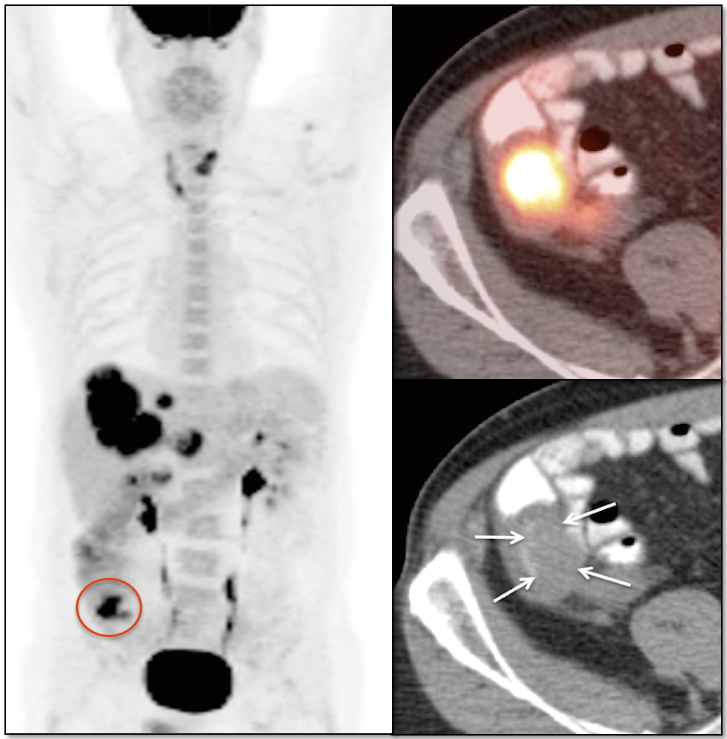

Recurrence & Restaging: (Most common indication)

• Rising tumor markers & negative (or indeterminate) CT scan.

• Restaging known recurrence, especially if surgery is contemplated.

Metastases:

The most common sites of metastatic disease include the lymph nodes (regional & distant), liver, lung, peritoneal cavity, bones, brain and adrenal glands.